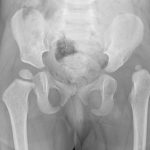

Hip dysplasia refers to underdevelopment of the hip joint and is most common in girls of Caucasian descent.

The hip is a ball-and-socket joint, in hip dysplasia, the socket

does not develop properly and is shallow compared to a normal hip. More like a

saucer than a cup. Sometimes, the hip may be completely dislocated, or out of

joint.

Risk factors for hip dysplasia include female gender, family

history of hip dysplasia and breech presentation. Hip dysplasia is also

associated with certain syndromes.

If left untreated, hip dysplasia leads to early hip arthritis

and pain, requiring hip replacement surgery at a young age. Untreated

dislocated hip will lead to a short leg on the affected side, limping and lower

back pain. Hip dysplasia always requires treatment.

Hip dysplasia is diagnosed by ultrasound and clinical

examination in new-born babies. If you have any risk factors, ultrasound should

be performed. In older children, X-rays of the hips must be done.

In new-born babies, treatment consists of a brace known as a

Pavlik harness. This brace must be worn full-time with regular check-ups

including ultrasound of the hip, to monitor the development of the hip joint.

This treatment is successful in most cases, but if not, surgery may be required.

Importantly, the sooner the hip is put back in joint, the better the expected

outcome.